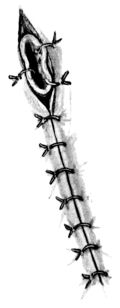

| 261. | Thyrotomy | 490 |